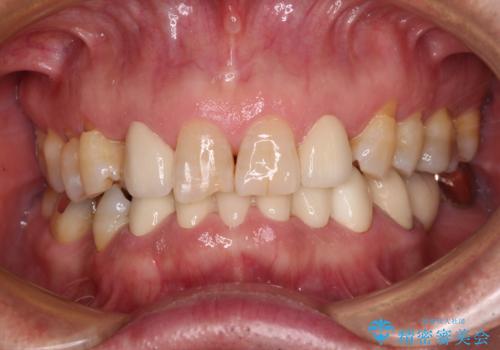

下顎の乳歯は支台歯として機能することは困難と思われたので、事前に抜歯をし、上顎の矯正治療終了のタイミングに合わせて、セラミックブリッジにて補綴治療することとしました。

前歯部はディープバイトという、上顎前歯が下顎前歯に深く覆い被さる咬合であったので、理想的には全顎矯正が必要となりますが、今回は患者希望により前歯部のみの部分矯正で対応しました。そのため下顎犬歯の神経を取り除くことになってしまったのは心残りであります。